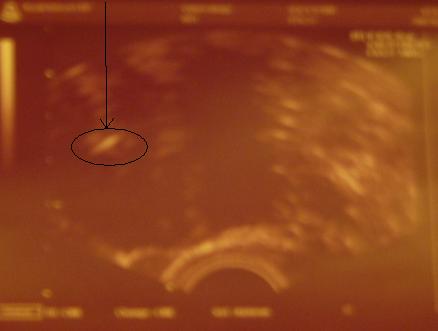

Tegnap Kata megírta, hogy a lánykának kinőtt a kukaca, így fiúcskánk lesz. Ha nem gond rakok róla egy képet. Éppen mosolyog, és a méhfalat simizi.